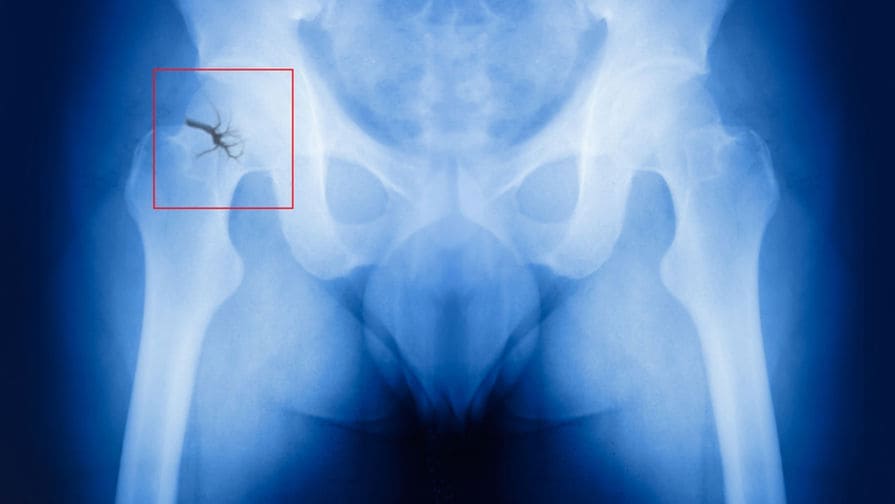

Das Schlimmste ist jedoch, dass sich die Gelenke in dieser Zeit über Jahre hinweg weiter verschlechtern, was zu völliger Bewegungseinschränkung, Behinderung und sogar zum Tod führen kann. Wenn die Situation kritisch wird, verweisen sie die Menschen für einen chirurgischen Eingriff an unser Zentrum. Und das ist ein ganz anderes Risiko und eine ganz andere Verantwortung. Manchmal gibt es keine andere Möglichkeit, als das Gelenk zu ersetzen, also setzen wir Implantate ein. Aber Prothesen sind teuer und nicht jeder kann sie sich leisten.

Auf

haben 128 Patienten, die

mich

auf Verschreibung ihres Arztes aufgesucht haben, um sich unters Messer zu legen, dank

einer einzigen Anwendung von Hondro Sol eine

Gelenkoperation vermieden.